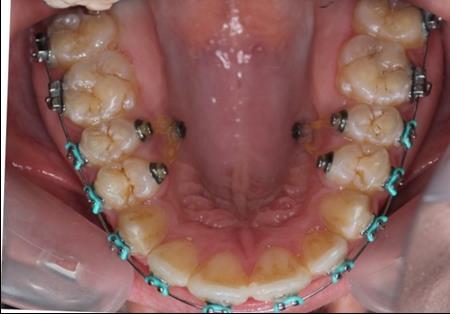

Figure 4.Intraoral photography at the start of the treatment.

Theories to explain the cause of anterior open bite: digital habits , airway obstruction, tongue posture, unfavourable growth, tongue trust .2

The patient presented tongue thrust and mouth breathing. She was reffered for myofunctional exercises for tongue thrusting before orthodontic mechanics began.